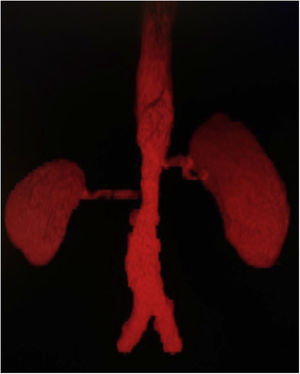

Presentación de casoPaciente masculino de 20 años, de nacionalidad mexicana, sin antecedentes familiares de importancia, quien comienza a los 16 años con cuadro de dolor y claudicación de extremidades inferiores, fatiga y elevación de cifras de tensión arterial. Durante la exploración física se observa asimetría de pulsos poplíteos y pedios, soplo abdominal y discrepancia de valores de tensión arterial>10mmHg en miembros superiores respecto a inferiores. Se inicia abordaje de hipertensión arterial secundaria; inicialmente se excluyen endocrinopatías, después se realiza angiotomografía computarizada con reconstrucción tridimensional (fig. 1), en la cual se observa estenosis del 70% en la aorta abdominal inframesentérica que involucra ambas arterias renales a nivel del ostium. Asimismo, los troncos supraaórticos no muestran lesiones, se detecta elevación de reactantes de fase aguda, proteína C reactiva 18,1mg/dl y velocidad de sedimentación globular 64mm/h. Con esta información se presentan criterios de clasificación de AT. La función renal basal se observa conservada, la creatinina sérica es de 0,58mg/dl y la tasa de filtrado glomerular 146ml/min. Se inicia tratamiento inmunosupresor con esteroides a 50mg/día de prednisona (1mg/kg/día), dosis de reducción hasta 20mg/día a los 6 meses de seguimiento y dosis de 5mg/día después de los 12 meses. Además, se administra metotrexate hasta 15mg/semana, anticoagulación con rivaroxaban y antihipertensivo con losartan y nifedipino. Al tercer año de seguimiento se presenta incremento de creatinina sérica, eritrocituria de 20 glóbulos rojos por campo y albuminuria en rango subnefrótico 1441mg en 24h. Se realiza ultrasonido renal con morfología y tamaño normales, riñón derecho 9,3×6,6×5cm, riñón izquierdo 10,2×7,4×5,1cm en sus ejes longitudinal, anteroposterior y transverso, respectivamente.

Los criterios de clasificación para esta patología obligan a tener evidencia de alteración angiográfica, ya sea mediante angiografía, o mediante angiorresonancia magnética o angiotomografía computarizada. En el paciente se utilizó este último por ser un método no invasivo que ofrece un excelente detalle anatómico tanto de la luz del vaso como de su pared; junto con la angiorresonancia magnética han reemplazado a la angiografía, considerado históricamente como el estándar de oro, puesto que este es un estudio invasivo y que no ofrece información de la pared del vaso7. En este caso se evidenció compromiso limitado a aorta abdominal y arterias renales, clasificado como numano IV, presente apenas en el 5,9% de los pacientes con diagnóstico de AT8.